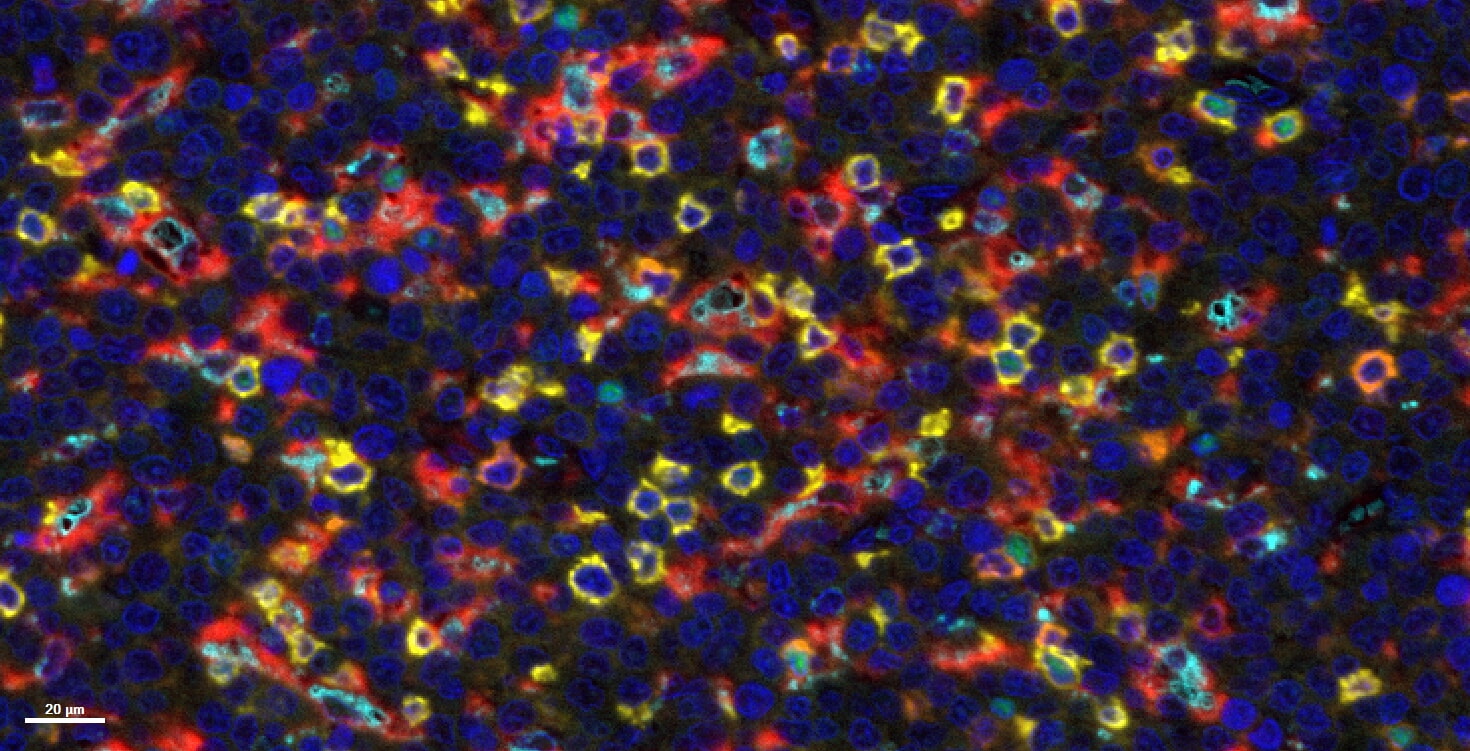

IMMUNO-CAR ZURICH

Innovative Zelltherapien für eine gezielte Krebsbehandlung

CCCZ Leuchtturmprojekt